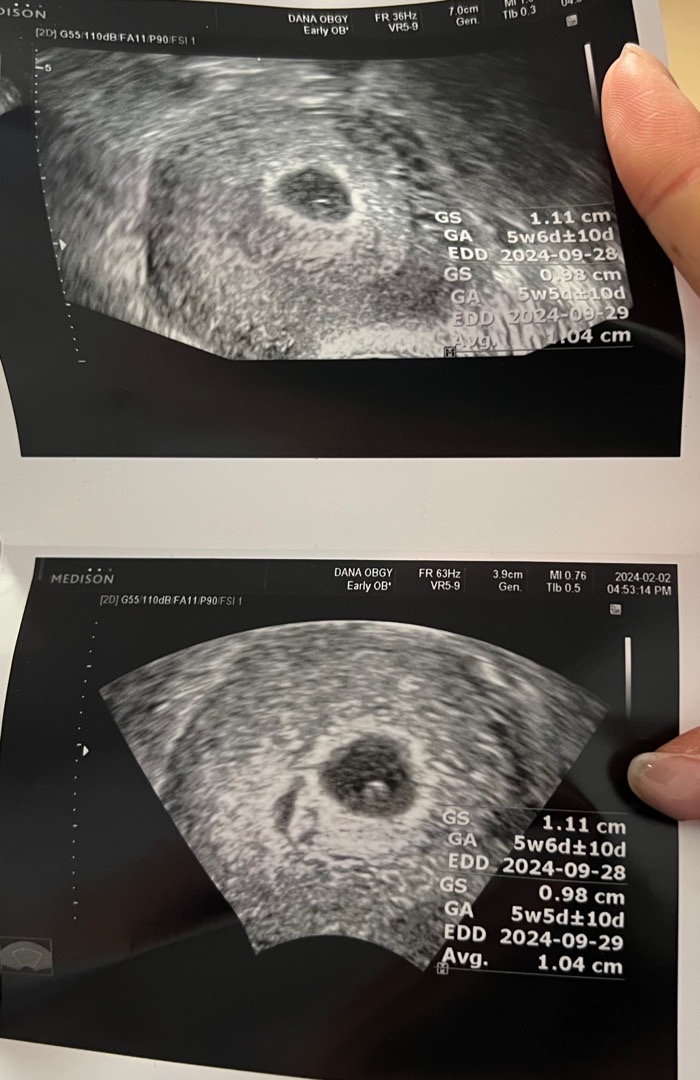

2/2에 춈파 보고왓는뎅 5주5일이구 난황도 보인다하는데 언제 링처럼 변할까용?약간 태극기 모양처럼 생겨서 넘 신기하기두 하네용 ㅎㅎ!!

저도 5주 6일에 난황까지만 보교 2주후에 오라고하셔서 7주5일에 가서 아기랑 심장소리까지 다 보고 왔습니다! 6주 후반이면 들으실 수 있지않을까요?? 혹시 못들으셔도 심장 깜빡이는건 보이실듯해요!

다음주만 되두 보시기겟는데용! 제거 5주5일에갓는데 난황 못봣는데 그러고 일주일잇다가 가니까 난황두 애기두 보구 심장 소리도 들었어요!